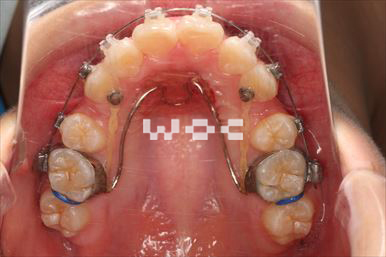

受け口・反対咬合エッジワイズ装置

特に装置の希望はなかったので、エッジワイズ装置を選択。

下顎両側臼歯部に歯科矯正用アンカースクリューを埋入し、下の歯列を後方へ移動しました。-

- 年齢:24歳女性

- 主訴:受け口を治したい

- 基本矯正料金:80万円

- 治療期間:1年3ヶ月

- 非抜歯